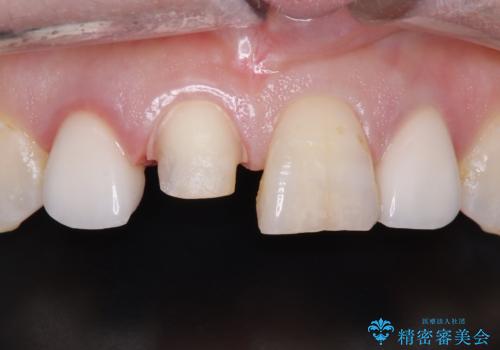

前歯のセラミッククラウン 詰め物が取れた

- 主訴:詰め物が取れた。

2日前に詰め物が取れ来院されました。中で虫歯が広がっている状態でした。歯科の治療が少し怖いとのことで静脈内鎮静を希望されました。

隣と同じように白くしたい、再治療を減らしたいとのことで、セラミッククラウン(スペシャル)で治療することとなりました。